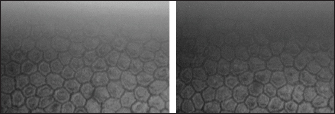

All enucleated eyes were included in the study. All eyes had a transparent cornea. Using the contact specular microscope, it was possible to assess the corneal endothelium of the bovine eyes and obtain clear images of all analyzed eyes. A regular and continuous pattern of juxtaposed cells, with sharp borders, was observed in the central region of the bovine corneal endothelium (Fig. 5). The average values of cell density and endothelial morphology are different from the values found in other species already studied (Table 1).

Fig. 5. Specular photomicrographs of the corneal endothelium of a bovine obtained using a contact specular microscope.

The mean ECD of the central area was 1,277 cells/mm2. Regarding the morphology, mainly cells with six (74.3%), five (14.7%), and seven sides (10%) were found, along with four-sided and eight-sided cells (Table 2).

In most vertebrates the shape of the normal corneal endothelial cells was mainly hexagonal, pentagonal, and tetragonal cells (Yee et al., 1987; Collin and Collin, 1998). In this study, the predominant morphological pattern was hexagonal (74.3%). There was no significant difference between in the endothelial morphological findings for the right and left eyes, which is in agreement with previous findings (Albuquerque et al., 2015; Bercht et al., 2015; Brambatti et al., 2017; Coyo et al., 2018a, 2018b).